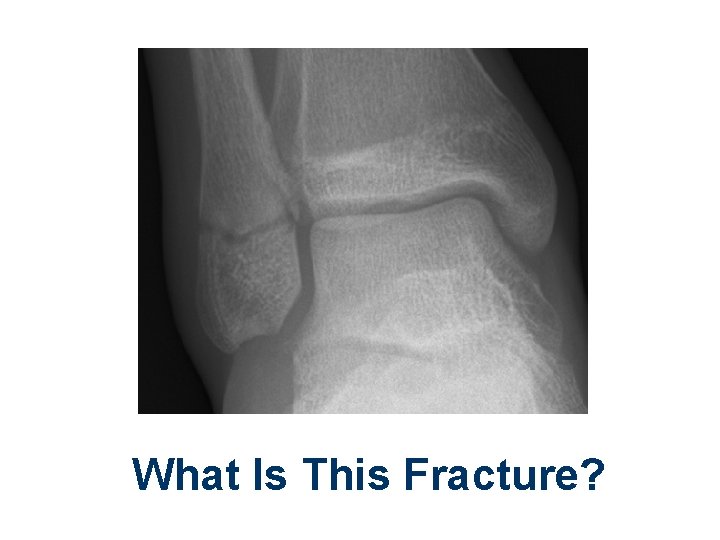

What Is This Fracture?

Lateral Malleolus Fracture. How Should It Be Immobilized?